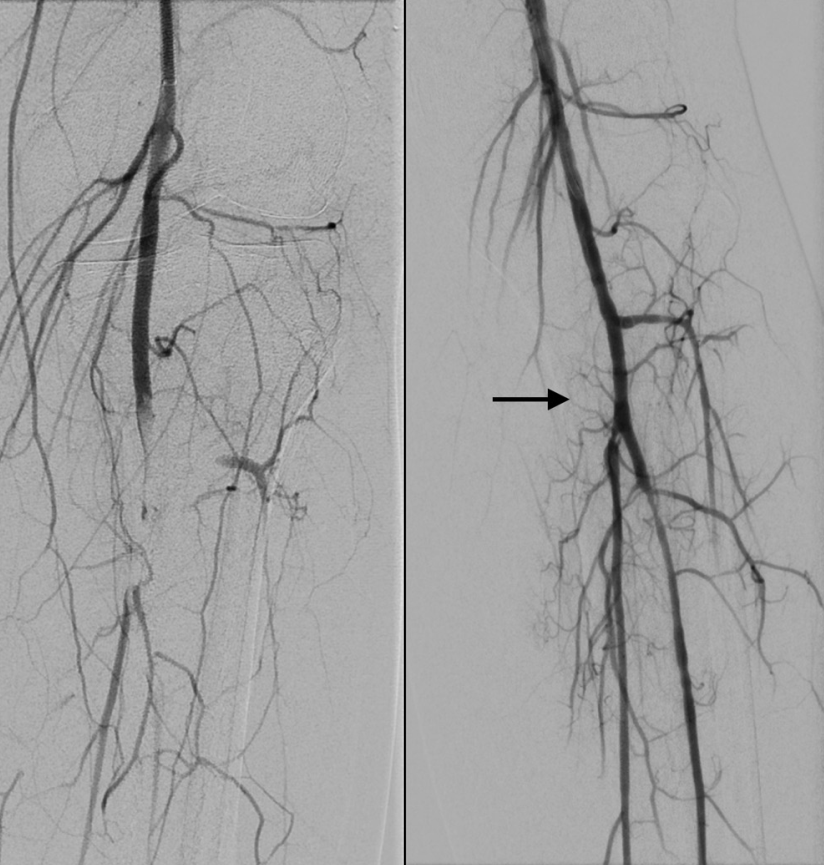

患者接受了紧急血管造影,发现左下肢腘动脉远段、胫前动脉和胫腓干有多发栓子(图2)。通过抽吸取栓术从左下肢抽出了白色胶状物,显微镜下标本显示为黏液瘤的细胞结构和基质,术后左下肢灌注恢复。右下肢血管造影发现踝部有小栓子,但侧支循环和足底弓灌注存在,未采取干预措施(图3)。

图2.血管造影

(A)左下肢腘动脉远段、胫前动脉和胫腓干有多发栓子; (B)抽吸后血管造影显示闭塞完全再通(箭头)